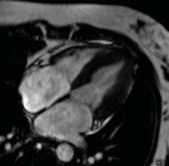

Our most energy-efficient 1.5T MRI with DryCool Technology

siemens-healthineers.ca/magnetom-flow

Ushering in a new era of sustainable and helium-independent MRI, MAGNETOM Flow.Ace (60cm bore) and MAGNETOM Flow.Elite (70cm bore) are now available in Canada.

They empower you across the entire imaging process from start to finish with unmatched workflow simplicity, elevated patient experience and pioneering AI-enhanced imaging for high-quality results at unrivaled speed.

• Virtually helium-free 1.5T MRI with DryCool technology and sealed for life magnet

• Our most energy-efficient 1.5T MRI, bringing 30-40% energy savings

• No quench-pipe and an ultra-compact footprint of only 25 m2

• Complete patient-centric workflow with BioMatrix Contour coils

• Smart and intelligent AI guidance with Deep Resolve and myExam Companion

Core exams

Growing imaging

Oncology

Rising cancer cases

Cardiology

Increasing indications for CMR